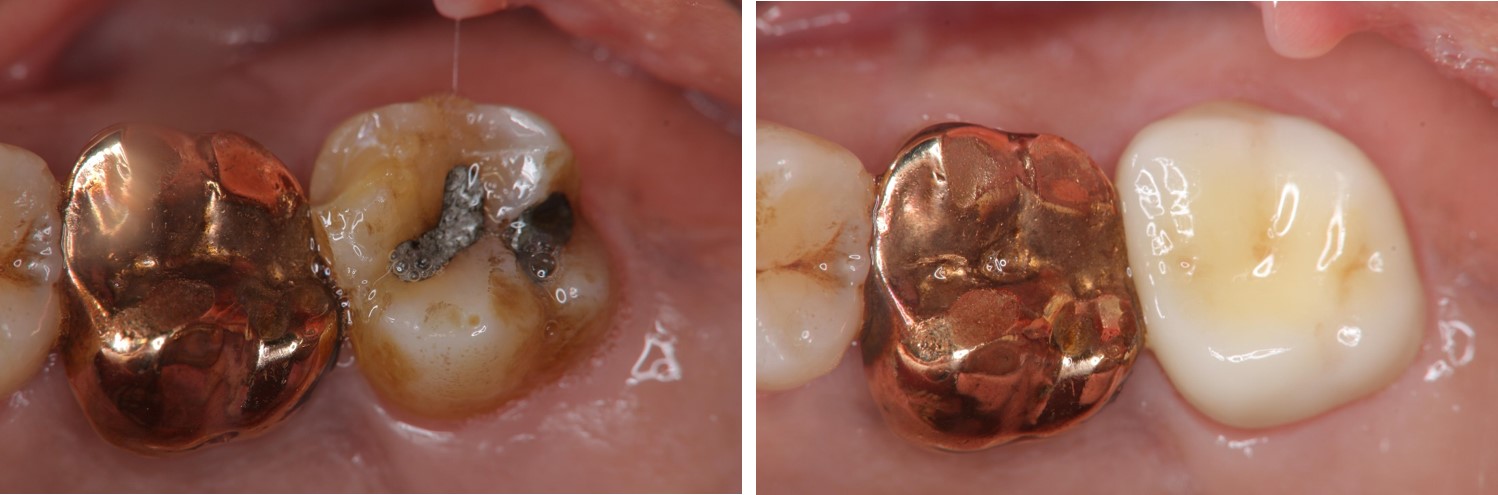

後牙一體成型全鋯冠-蛀牙-#44

審美牙科

全瓷冠

後牙一體成型全鋯冠-蛀牙-#27